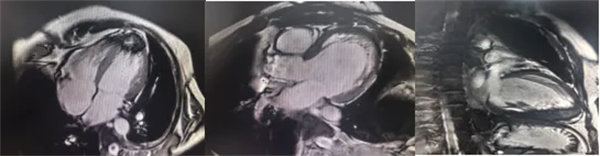

在常規心臟MRI檢查中,醫學影像科發現患者心肌異常表現,考慮鐵過載性心肌病,為明確診斷要進一步加做鐵定量技術,加掃T2 mapping序列。CMR鐵定量技術是目前評估心肌鐵含量的“金標準”,能夠快速、無創、精準量化心肌內鐵沉積程度,檢查結果提示患者局部心肌T2*值顯著低于正常范圍,符合鐵過載性心肌病的診斷標準。

CMR是目前唯一能定量檢測組織鐵負荷的無創影像學手段,主要依賴其 T2*mapping技術測量的T2*弛豫時間(T2*值)間接量化組織鐵含量。當CMR檢測出心肌T2*<20 ms時,初步診斷心肌鐵過載,T2*值<10-15ms時,提示心功能受損風險顯著增加。T2值越低,鐵沉積越嚴重。目前T2*mapping技術檢測T2*已作為臨床診斷肝臟、心肌鐵過載的首選無創檢查,也被用作隨訪工具評估疾病進展和療效。

肝臟和脾臟信號改變 矢狀位梯度回波定位圖像可顯示肝臟和脾臟信號降低,提示肝脾鐵沉積,T2*>6.3及R2*>160/s表現中度鐵過載。